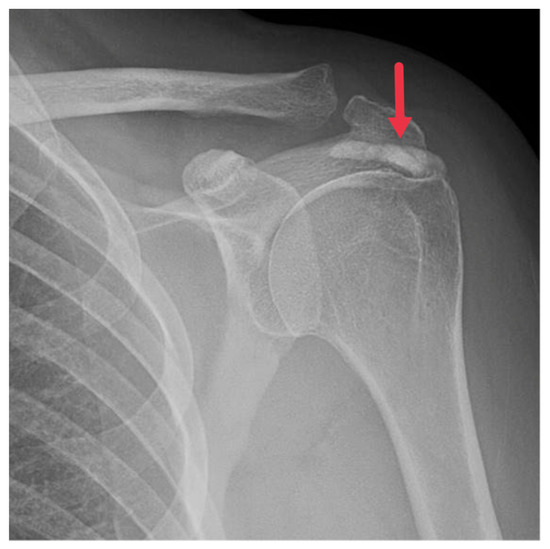

Regarded as the first line of imaging modality for HADD diagnosis, plain radiographs capture the hallmark feature of HADD: amorphous, nebulous densities in soft tissues. These hydroxyapatite densities mainly encircle joints, particularly the shoulder (Figure 1), but can also inhabit unconventional regions like the hip, wrist, and spine.

Figure 1. Frontal radiograph of the left shoulder demonstrating a well-defined calcification in the supraspinatus tendon (red arrow).

Advanced cases of HADD might exhibit these deposits in conjunction with bone erosion or cortical irregularities [3,8]. The scattered distribution of the calcified material accounts for the nebulous appearance of these deposits on radiographs, setting HADD apart from other conditions with similar radiographic findings [3,8,21]. The location of these deposits could provide valuable insights for diagnosing HADD. Instances of deposits in areas like the hip or wrist might point towards HADD in patients with discomfort in these areas.